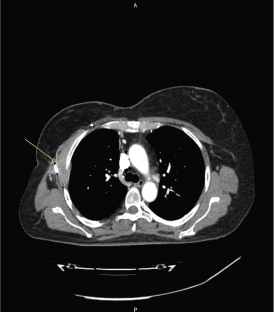

A 57-year-old woman with a previous history of aesthetic surgery for breast reduction presented with a subcutaneous mass in the right axilla. The patient underwent a computed tomography (CT) scan, showing a contrast-enhanced solid mass in the right axilla, with a total extra-pleural growth (Figure 1). A positron emission tomography (PET)-CT scan (Figure 2), showed an intense Fludeoxyglucose (FDG) uptake of the lesion, and a subsequent ultrasound (US)-guided biopsy disclosed mesenchymal tumour with uncertain malignant potential.

Figure 1. The axial CT scan at first diagnosis, showing a contrast-enhanced solid mass (arrow) in the right axilla, with a total extrapleural growth.